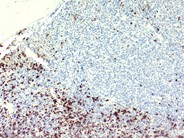

The intersect of the normal and leukemic marrow areas are evident at the higher magnification shown. Increased but scattered blasts can be seen in the area of normal hematopoiesis.